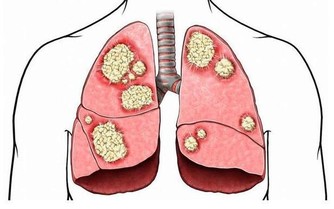

長時間宅在家的一個常見問題就是睡覺時間越來越晚,這對防範疾病絕對是不利的。因為缺乏睡眠會導致身體免疫力下降,病毒、細菌更容易趁虛而入。而且長期熬夜導致的免疫力下降,還會使部分癌細胞逃脫免疫監視,從而增加患癌風險!

後半夜(3:00~7:00)不睡,NK細胞的活性同樣下降。NK細胞是人體免疫系統裡抗腫瘤、抗病毒的“特種部隊”,它的活性下降了,我們的免疫系統便不再強悍,癌細胞也就有了可乘之機。

此外,缺乏睡眠會導致血壓上升、內分泌和代謝異常、炎症反應炎症物質增多。在之前的課程裡我們已經講解了炎症物質與癌症的關係,過量生產的炎症物質積蓄在體內會誘發、加重癌細胞的生長與擴散,這也是睡眠不足容易引發癌症的原因之一。